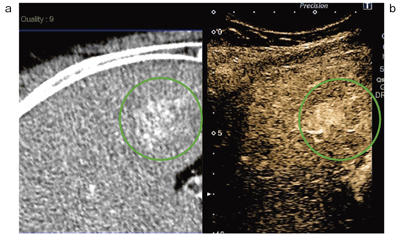

Smart Fusionを使った肝がん治療の実際の症例を提示する。60歳代の男性で,C型肝硬変,S6に2cmの単発・初発の肝がん症例である(図3〜6)。

まず,ソナゾイドによる造影超音波を行うが,Aplio500では造影性能も向上しており,空間分解能も高く,肝臓の浅いところから深いところまで均一な,コントラスト分解能の良い造影像が得られている。フュージョンすると,CTの動脈相とよく一致した所見で,腫瘍の範囲がさらに明瞭になる(図3)。

図3 CT(a)とソナゾイド造影Kupfferイメージ(b)のSmart Fusion 画面

両者の濃染像がよく一致している。